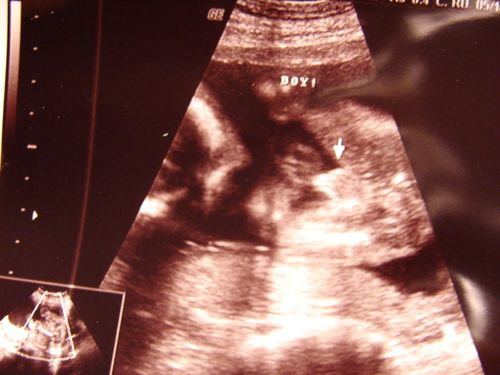

Yep. That's right. Baby #3 is a BOY!!! But, then again, I already knew that. We had our ultrasound today and we were all ecstatic to find out that our home will once again be blessed with even more testosterone!

His package.